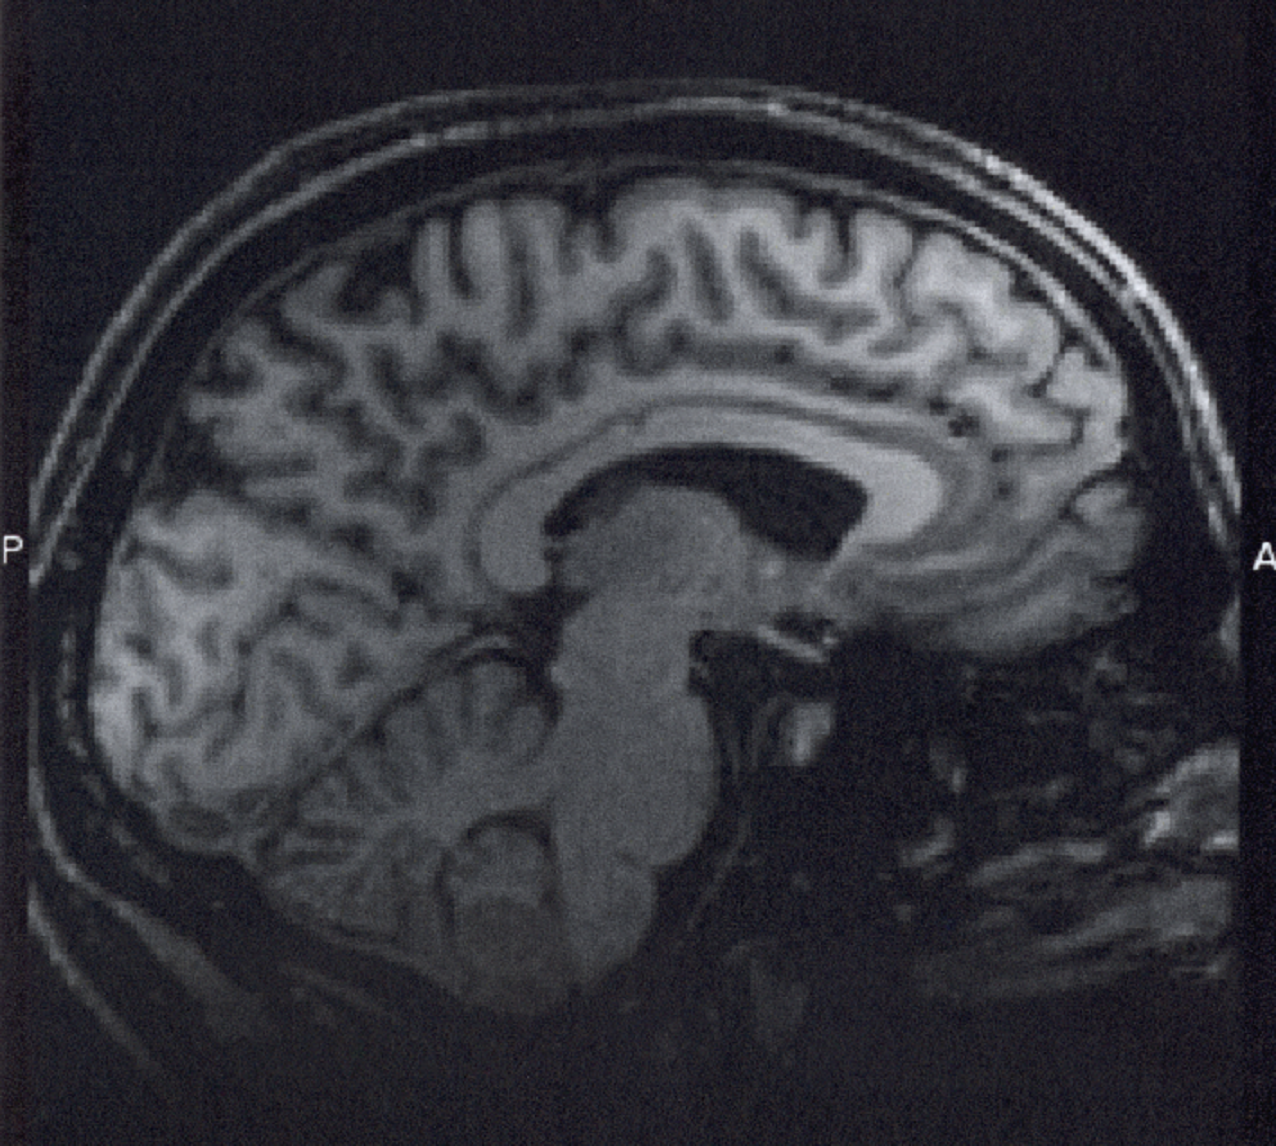

Los escáneres cerebrales de personas en estado de coma pueden ayudar a predecir si va a recuperar la conciencia, según un estudio publicado en la edición en línea de Neurology, la revista médica de la Academia Americana de Neurología (AAN). El estudio se centra en las conexiones entre las áreas del cerebro que juegan un papel en la regulación de la conciencia.

Para el estudio, se compararon los cerebros de 27 personas en estado de coma con lesiones cerebrales graves con los de 14 personas sanas de la misma edad. A todos los participantes se les realizaron resonancias magnéticas en el cerebro. Para aquellos en estado de coma, se llevaron a cabo las exploraciones después de eliminar todos los medicamentos sedantes de sus sistemas.

Todas las personas en estado de coma tenían una interrupción significativa en las conexiones con la corteza cingulada posterior. Estos cambios eran los mismos si la lesión cerebral se debía a un trauma o a la falta de oxígeno, por un paro cardíaco, por ejemplo.

Los investigadores encontraron sin embargo, según la nota de prensa de la Asociación Americana de Neurología, que la coordinación de la actividad entre la corteza cingulada posterior y una zona concreta del cerebro, la corteza prefrontal medial era significativamente diferente entre los que llegaban a recuperarse del coma y los que se quedaron en un estado de conciencia mínima o en estado vegetativo. La coordinación entre las dos áreas del cerebro era la misma en los participantes sanos y en los que recuperaron la conciencia.